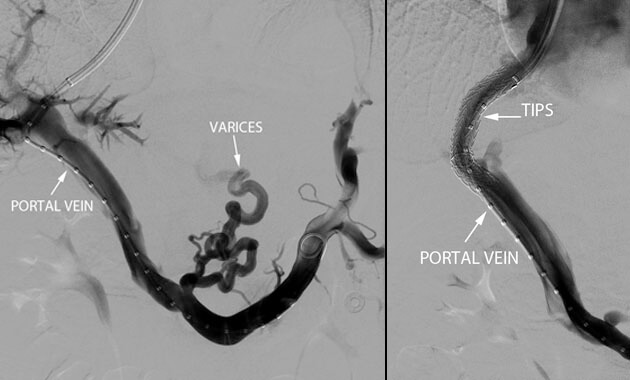

Portal Hypertension

- Conditions: Portal hypertension, esophageal varices, gastric varices, variceal bleeding, ascites, portal vein thrombosis, Budd-Chiari syndrome

- Services: Transjugular intrahepatic portosystemic shunt (TIPS), Balloon-assisted retrograde transvenous obliteration (BRTO), portal vein recanalization, paracentesis, abdominal PleurX placement